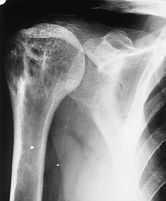

Las radiografíasrealizadas en el húmero muestran (fig. 1A) un desplazamientode la cavidad medular e imágenes radiolucentes con aumentode densidad, al tiempo que hay pérdida de la corticalnormal. En la tomografía axial computadorizada (TAC) (fig.1B) se puede apreciar rarefacción en parches de huesostubulares con atrofia interna y agrandamiento de la corteza. Laslesiones descalcificadas revelan un margen bien definidoesclerótico con una superficie interna densa y unasuperficie externa que evoluciona gradualmente a hueso normal. Elresto del hueso muestra una apariencia normal.

Figura1A.